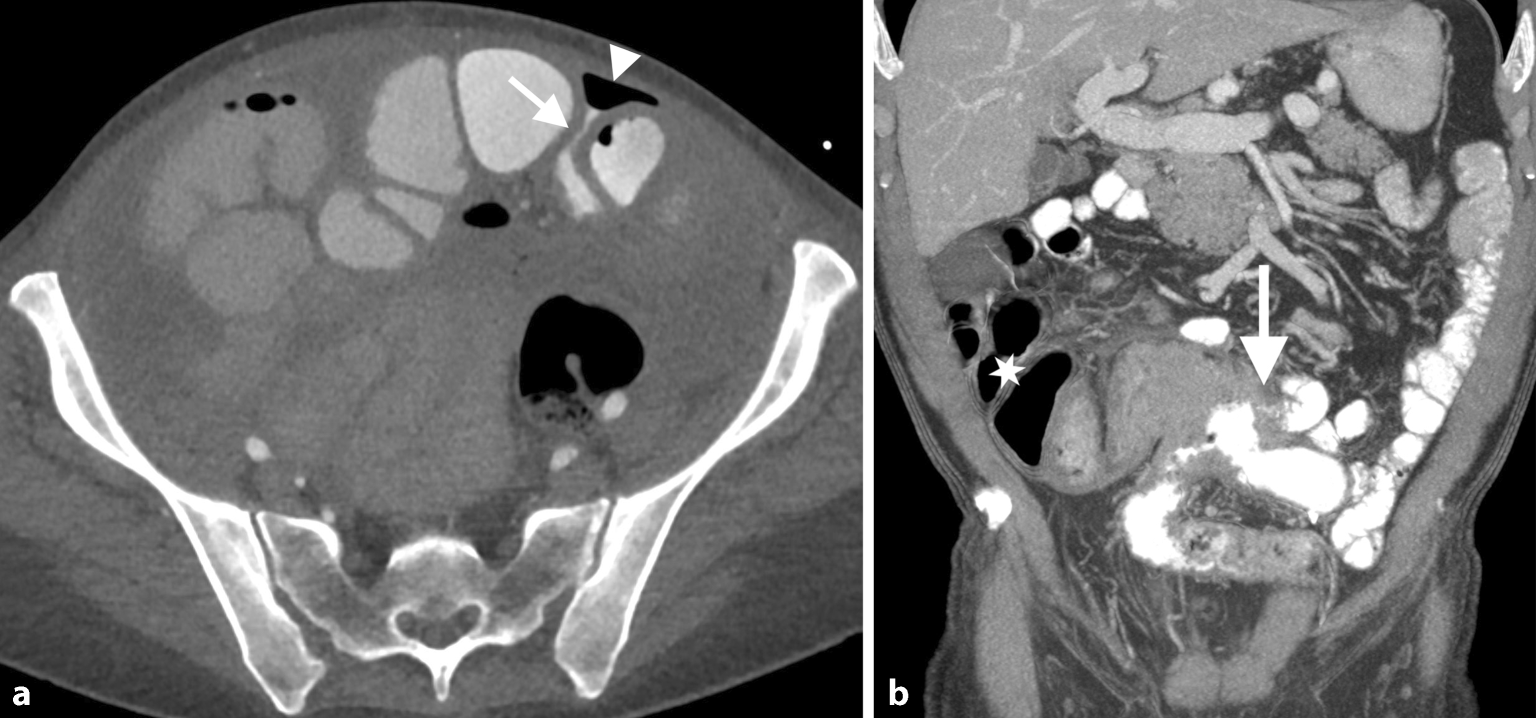

Der großzügigere Einsatz von positivem Kontrastmittel wird allerdings von einigen Experten zunehmend befürwortet, wobei die vergleichsweise geringe Verlängerung der Untersuchungszeit um etwa 30–40 min als klinisch vertretbar angesehen wird [17]. Bei bestimmten Fragestellungen, wie dem postoperativen Nachweis eines Dünndarmlecks, ist die Gabe von positiv oralem Kontrastmittel grundsätzlich indiziert (Abb. 6).

Zwei unterschiedliche Patienten mit positivem oralen Kontrastmittel. a Patientin mit peritoneal metastasiertem Appendixkarzinom nach hypertherm intraperitonealer Chemotherapie (HIPEC): Aufgrund steigender Entzündungsparameter und abdominaler Schmerzen erfolgte eine Computertomographie (CT), die ein kleines Dünndarmleak (Pfeil) mit begleitender extraluminaler Gasansammlung im ventralen Abdomen zeigt. b Patient nach Ileosigmoidostomie bei ausgedehntem Morbus Crohn und Bauchschmerzen sowie progredienter Diarrhö: Das koronale CT-Bild zeigt eine ausgedehnte Raumforderung im Bereich der Anastomose (verifiziert als Lymphom) und eine Fistelbildung (Pfeil); zu beachten ist das fehlende intraluminale Kontrastmittel vor der Anastomose durch die fistelbedingte Umgehung (Stern)